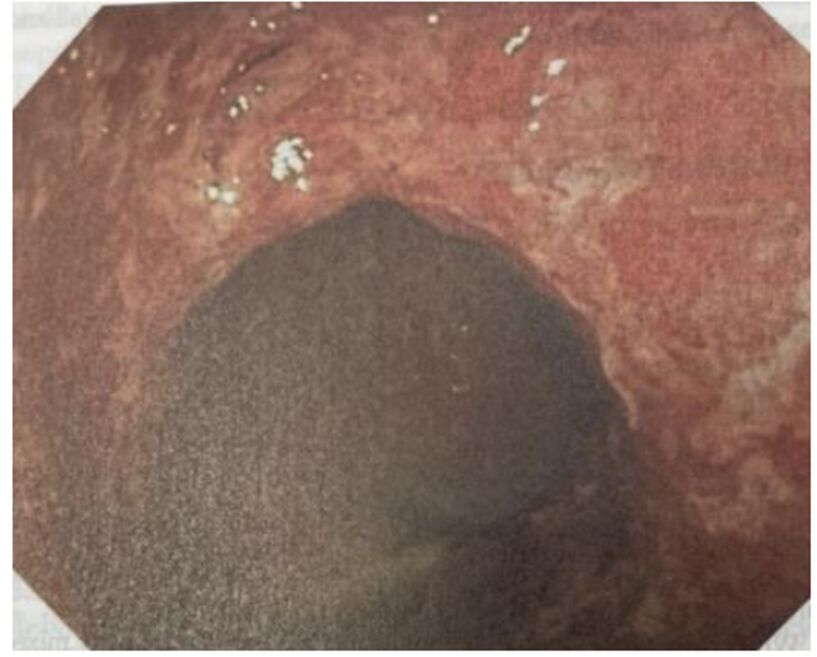

16. 一位55歲女性病患因端坐呼吸與動喘一週而來住院。身體診察發現血壓90/56毫米汞柱,心跳每分 鐘102下,頸靜脈怒張,心音低遠併第三心音,肺部有囉音,雙下肢小腿與腳部水腫。心電圖如圖一。心臟超音波呈現左心室擴大,瀰漫性左心室收縮功能異常,左心室射出分率(left ventricle ejection fraction)為25%。心臟磁振造影檢查如圖二A與B。經食道心臟超音波如圖二C與D。請問下列敘述何者錯誤?

(1)該病患的心電圖呈現 low voltage in frontal leads (2)該病患心電圖呈現心房顫動 (3)該病患之心臟磁 振造影影像檢查呈現左心室心肌緻密化不全(left ventricular non-compaction) (4)該病患之心臟磁振造影影 像檢查呈現急性心肌發炎 (5)該病患應使用口服抗凝血劑 (6)這種疾病有時是因肌節(sarcomere)基因異常 引起 (A) (1)+(3)+(6)。 (B) (2)+(3)+(5)。 (C) (2)+(4)。 (D) (2)+(4)+(5)。